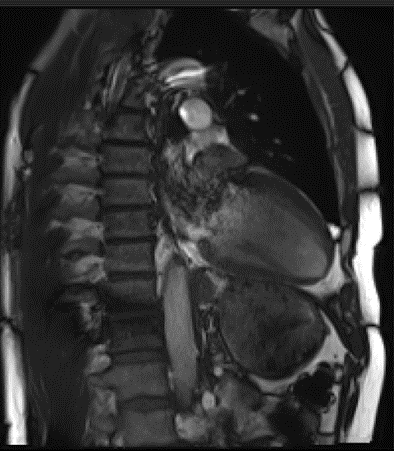

STAMP-2

Une étude sur 280 patients atteints de PVMLe Prolapsus Valvulaire Mitral (PVM) est une atteinte de la valve mitrale dont la prévalence est de 2-3% dans la population générale. Cette atteinte considérée bénigne peut évoluer vers une fuite mitrale d’intensité variable ou des complications rythmiques. Les symptômes rythmiques peuvent aller de simples extrasystoles isolées jusqu’à des arythmies ventriculaires graves causes de mort subite. More

Début : 2021L’objectif de cette étude multicentrique est de rechercher des marqueurs prédictifs d’évolution défavorable à 3 ans chez des patients atteints d’un Prolapsus Valvulaire Mitral (PVMLe Prolapsus Valvulaire Mitral (PVM) est une atteinte de la valve mitrale dont la prévalence est de 2-3% dans la population générale. Cette atteinte considérée bénigne peut évoluer vers une fuite mitrale d’intensité variable ou des complications rythmiques. Les symptômes rythmiques peuvent aller de simples extrasystoles isolées jusqu’à des arythmies ventriculaires graves causes de mort subite. More). Pour en savoir + -

STAMP

Une étude sur le PVMLe Prolapsus Valvulaire Mitral (PVM) est une atteinte de la valve mitrale dont la prévalence est de 2-3% dans la population générale. Cette atteinte considérée bénigne peut évoluer vers une fuite mitrale d’intensité variable ou des complications rythmiques. Les symptômes rythmiques peuvent aller de simples extrasystoles isolées jusqu’à des arythmies ventriculaires graves causes de mort subite. More

Début : 2016 / Fin: 2021Le but de cette étude est de caractériser les lésions tissulaires du cœur chez les patients ayant un Prolapsus Valvulaire Mitral (PVMLe Prolapsus Valvulaire Mitral (PVM) est une atteinte de la valve mitrale dont la prévalence est de 2-3% dans la population générale. Cette atteinte considérée bénigne peut évoluer vers une fuite mitrale d’intensité variable ou des complications rythmiques. Les symptômes rythmiques peuvent aller de simples extrasystoles isolées jusqu’à des arythmies ventriculaires graves causes de mort subite. More) en complément d’une analyse du rythme cardiaque (recherche d’atteinte rythmique). A terme, l’objectif est de modifier les recommandations de prise en charge pour proposer un suivi plus adapté aux patients. Pour en savoir + -